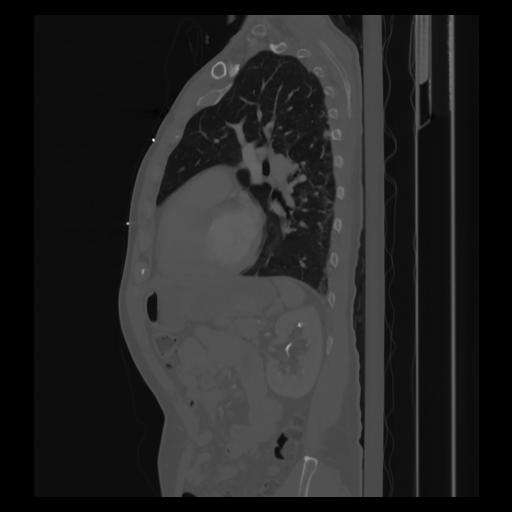

30 CUERPO,CE,Sagittal,3.000,CUERPO,Sagittal,